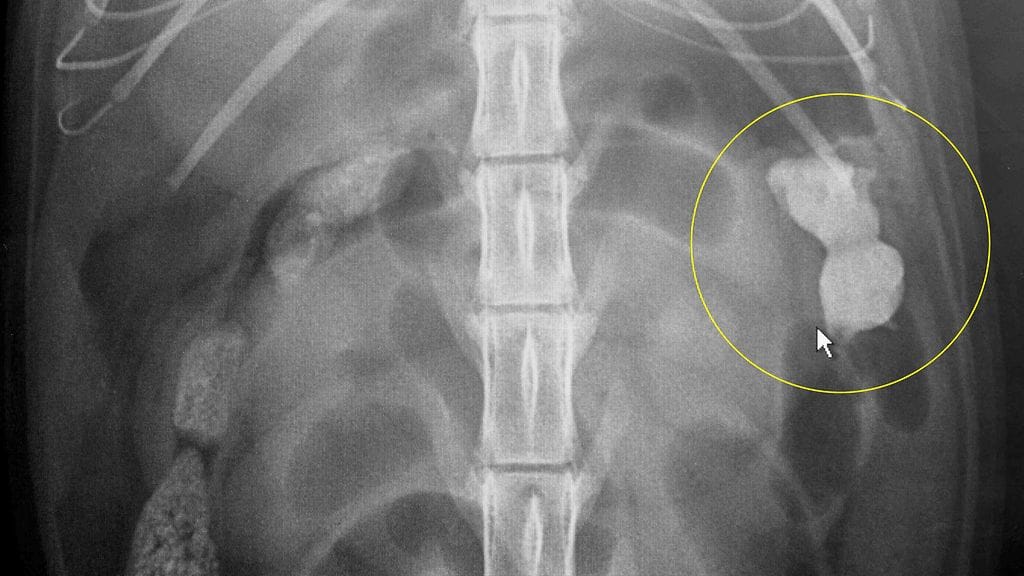

Kitty-kissa melkein kohtasi loppunsa itsensä mukaan nimetyn muovilelun vuoksi. Kissa nielaisi vahingossa lelukissan, joka piti poistaa kissan suolistosta kirurgisesti.

Viisi senttiä korkea muovi-Kitty oli ehtinyt repiä kissan kudoksia ja uhkasi puhkaista suolen seinämän.